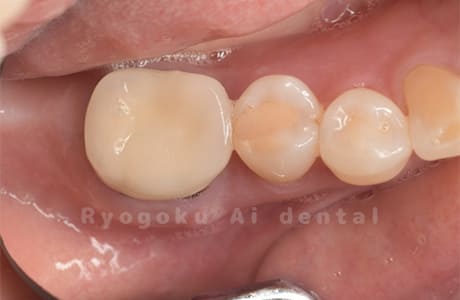

Case10

術前

術後

- 原因

- 左下6番欠損

-

- 治療内容

- インプラント治療

- 治療費用

- 約600,000円

左下の奥歯に歯を入れて欲しいとのことでご来院された患者様です。インプラント治療が最適とご提案させて頂き、治療を行いました。経過も良好で、大変満足して頂けました。

<リスク・副作用>

治療後、痛みや違和感、出血、腫れなどが出る事があります。喫煙者、糖尿病などの方の場合、歯が生着しない場合があります。